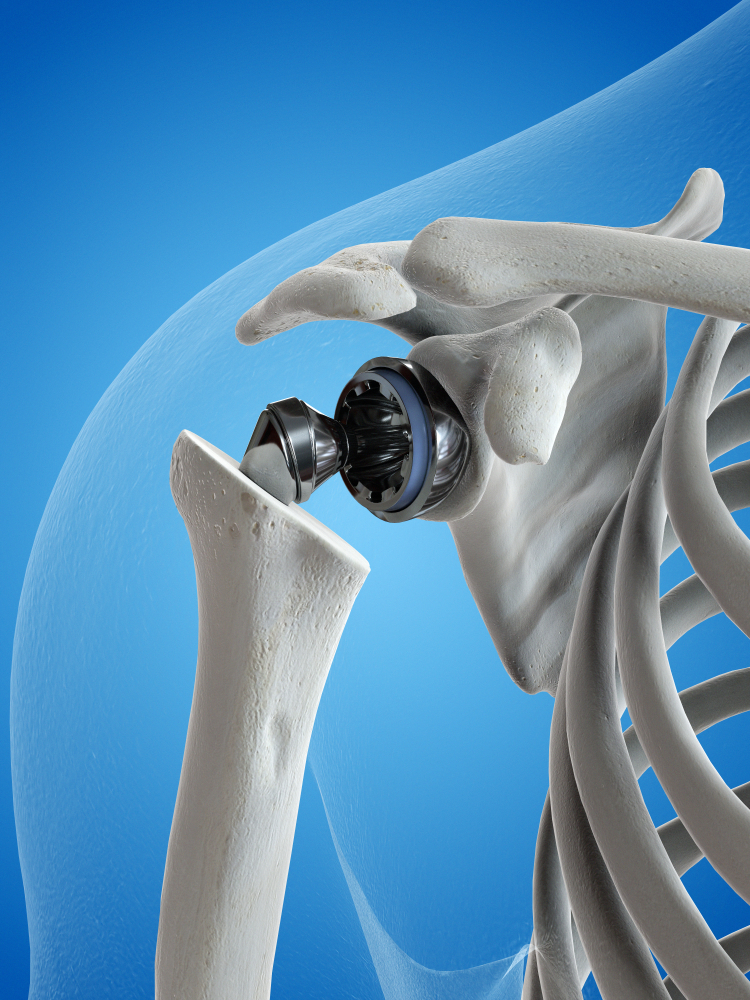

El hombro es una enartrosis lo cual quiere decir que el extremo redondo del hueso del brazo encaja dentro de la abertura en el extremo del omóplato. Este tipo de articulación permite mover el brazo en la mayoría de las direcciones.

Para el reemplazo total del hombro, el extremo redondo del hueso del brazo se reemplazará con una caña o vástago artificial que tiene una cabeza de metal redondeada. La parte de la cavidad (glenoide) del omóplato se reemplazará con una cubierta plástica y lisa (recubrimiento) que se sostendrá en el lugar con un cemento especial. Si sólo 1 de estos 2 huesos necesita ser reemplazado, la cirugía se denomina artroplastia parcial del hombro o hemiartroplastia.

El hombro es una enartrosis lo cual quiere decir que el extremo redondo del hueso del brazo encaja dentro de la abertura en el extremo del omóplato. Este tipo de articulación permite mover el brazo en la mayoría de las direcciones.

Para el reemplazo total del hombro, el extremo redondo del hueso del brazo se reemplazará con una caña o vástago artificial que tiene una cabeza de metal redondeada. La parte de la cavidad (glenoide) del omóplato se reemplazará con una cubierta plástica y lisa (recubrimiento) que se sostendrá en el lugar con un cemento especial. Si sólo 1 de estos 2 huesos necesita ser reemplazado, la cirugía se denomina artroplastia parcial del hombro o hemiartroplastia.